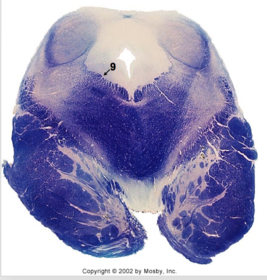

| Nucleus gracilis | |

| Accessory nucleus | |

| Medial longitudinal faciculus | |

| Pyramidal decussation | |

| Medullary pyramids | |

| Anterior spinocerebellar tract | |

| ALS | |

| Posterior spinocerebellar tract | |

| Spinal tract of V | |

| Spinal nucleus of V | |

| Nucleus cuneatus | |

| Fasciculus cuneatus | |

| Fasciculus gracilis | |

| Central canal | |